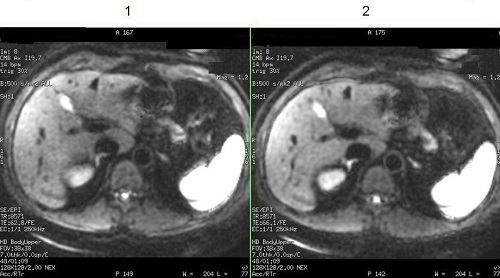

Gradient optimization for Diff All

Gradient Optimization for Diffusion All turns on Diffusion Gradopt All, which is selected from the Diffusion Direction menu located on the Diffusion tab.

Gradient Optimization for Diff All = 0 disables Diffusion Gradopt All Diffusion Direction resulting in an increased TE and thus reduced image quality.

Gradient Optimization for Diff All = 1 enables Diffusion Gradopt All Diffusion Direction resulting in decreased TE and a corresponding increased SNR in comparison to the standard All option. This is particularly important for abdominal images.

| Number | Description |

|---|---|

| 1 | Gradient Optimization for Diff All = 1 enables Diffusion Gradopt All Diffusion Direction. Note shortened TE = 62.8. |

| 2 | Gradient Optimization for Diff All = 0 disables Diffusion Gradopt All Diffusion Direction. Note the TE = 66.1. |